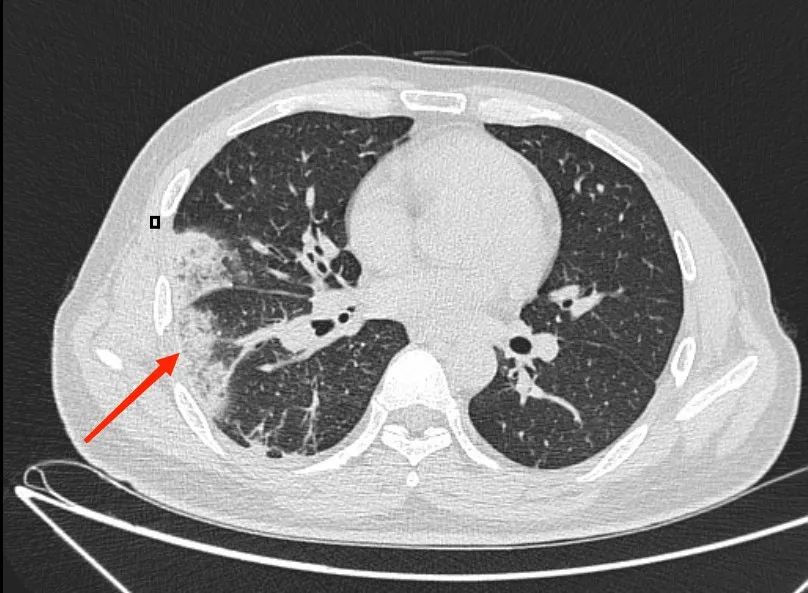

为尽快找到病因,肾内科紧急邀请肺部感染疾病专家团队——呼吸与危重症医学科三区专家前往会诊,专家对患者的肺部影像进行研究后,发现患者肺部病变部位周围可见“晕征”(环绕在病灶周围的磨玻璃影,而这对于感染来说最多见于肺曲霉菌病),专家们对曲霉菌感染在心中打了个问号。

考虑到杨先生病情较为复杂,呼吸与危重症医学科三区立即组织了多学科联合会诊。会上,专家们仔细回顾患者病史,他既往曾有颅内静脉血栓形成,且血脂远高于正常,高血脂的病人血液粘稠、流速缓慢,而这正是血栓形成的高危因素。杨先生的胸痛伴有咯血痰,肺部影像学改变为尖端指向肺门的阴影,除了肺部感染外,还有一个很重要且最容易让人忽视的疾病——肺栓塞!

不放过任何一个可疑因素,杨先生在医护人员的陪同下完善了肺动脉CTA检查,检查结果出来,果然是肺栓塞!杨先生肺部那一片片密度增高带有晕征的病变,以及抗感染治疗无效的疑点都得到了解释,是肺栓塞导致了肺梗死。

▲ 肺动脉CTA提示:肺栓塞